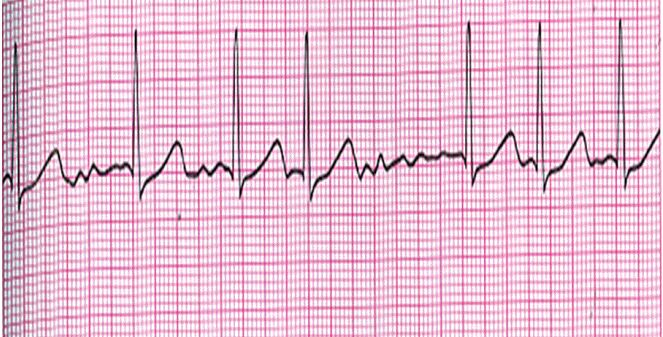

74.有關EKG判讀結果,下列何者正確? (A)心房顫動 (B)一度房室阻斷 (C)Mobitz二型房室阻斷 (D)心室性心律不整